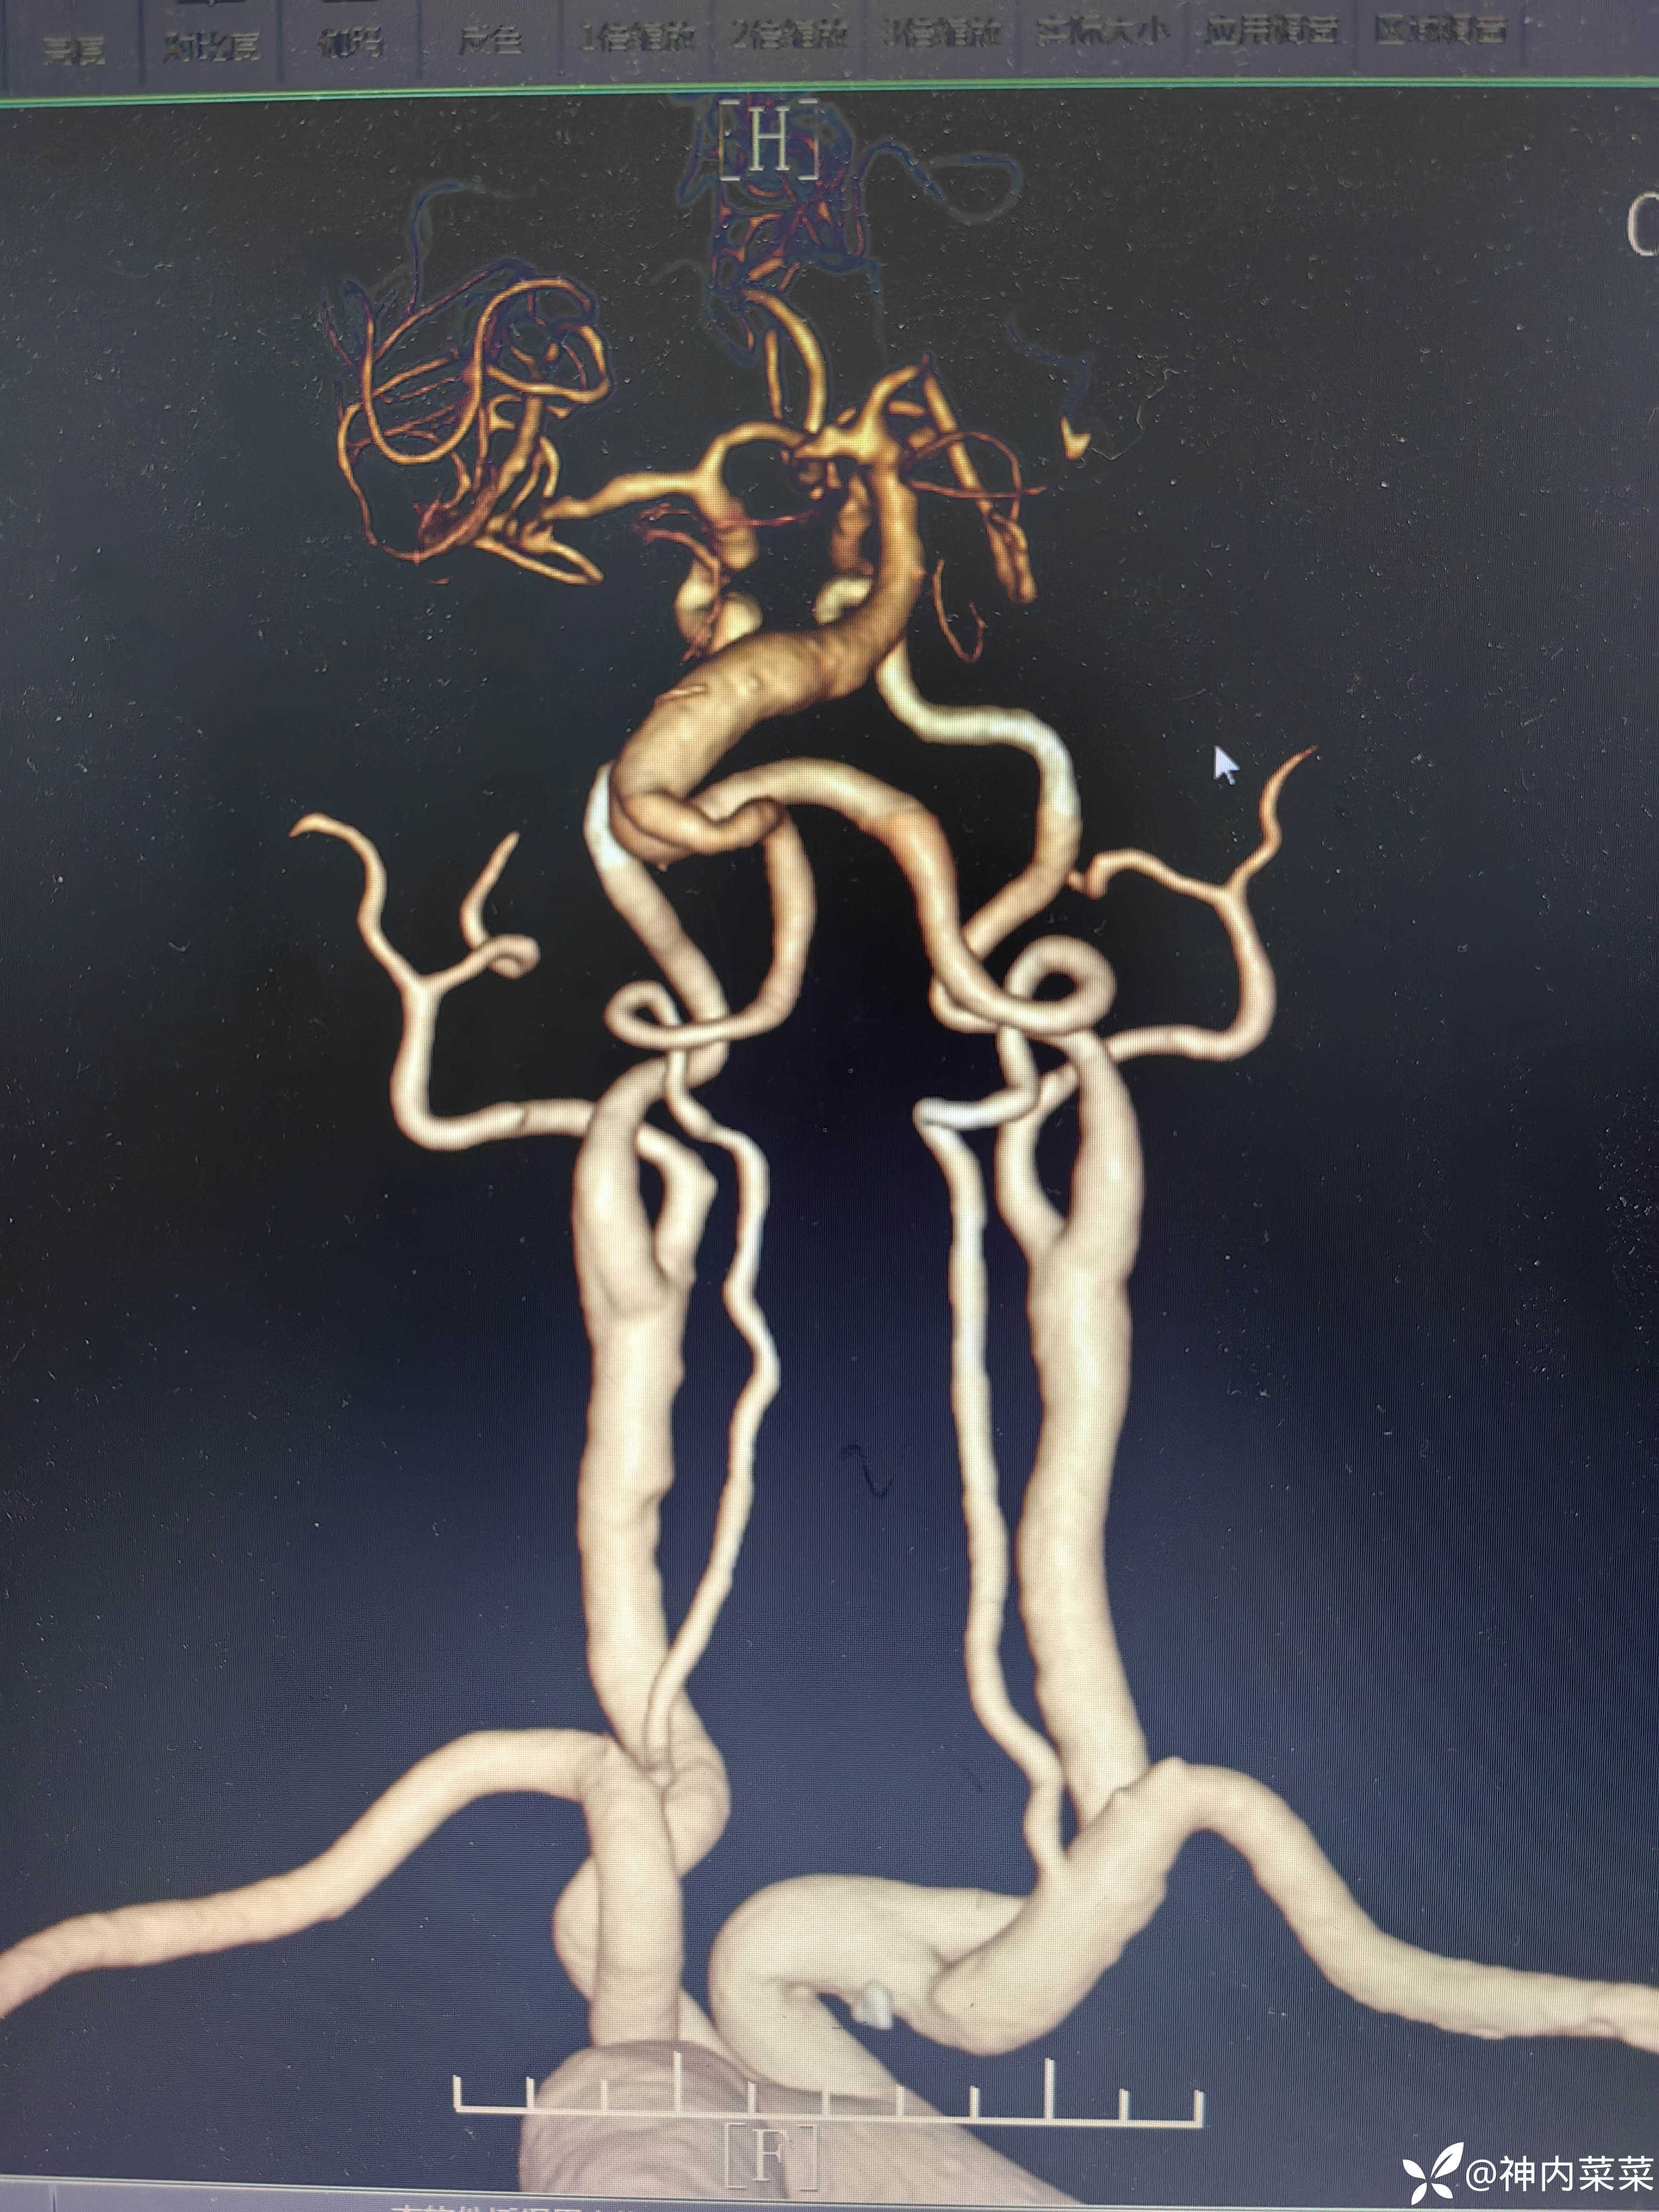

【患者信息】:男性,36岁

【主诉】:左侧肢体乏力1天

【现病史及既往史】:吸烟饮酒

【临床诊断】:基底动脉扩张延长

【治疗经过及结果】:抗血小板聚集稳定斑块治疗。